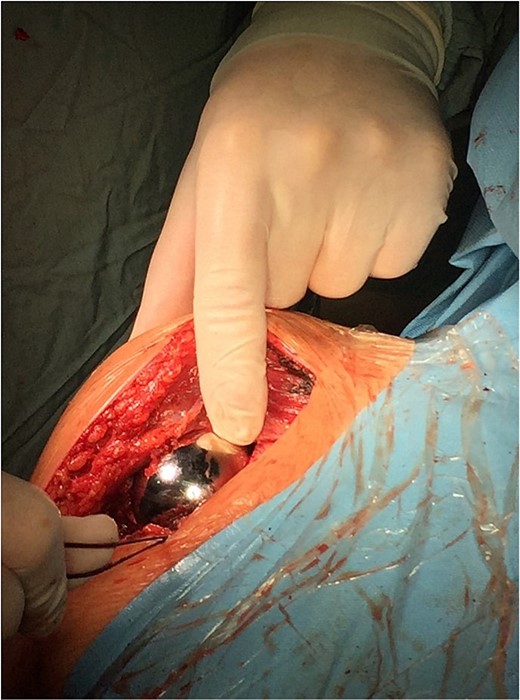

On 17 December 2020, an arthrosurface procedure on the humeral head was performed (i.e. replacement of the damaged articular surface with an implant that recreates its desired shape) using the OVO Motion Shoulder Arthroplasty System Med & Care. The surgery was performed under general endotracheal anesthesia. During the surgery, the beach chair position of the patient with delto-pectoral approach was performed. The arthrotomy was performed by temporarily dissecting the tendon of the subscapular muscle. Additionally, an intraoperative SLAP lesion was found, and the tenodesis of the long head of the biceps muscle was performed. The operation was performed according to the standard surgical procedures during which an endoprosthesis of the humerus head articular surface (OVO) (diameter 48 × 52 mm) was implanted and cemented.

The operation procedure took ~1 hr. Below are intraoperative photos after the endoprosthesis has been placed (Figs 6–8).